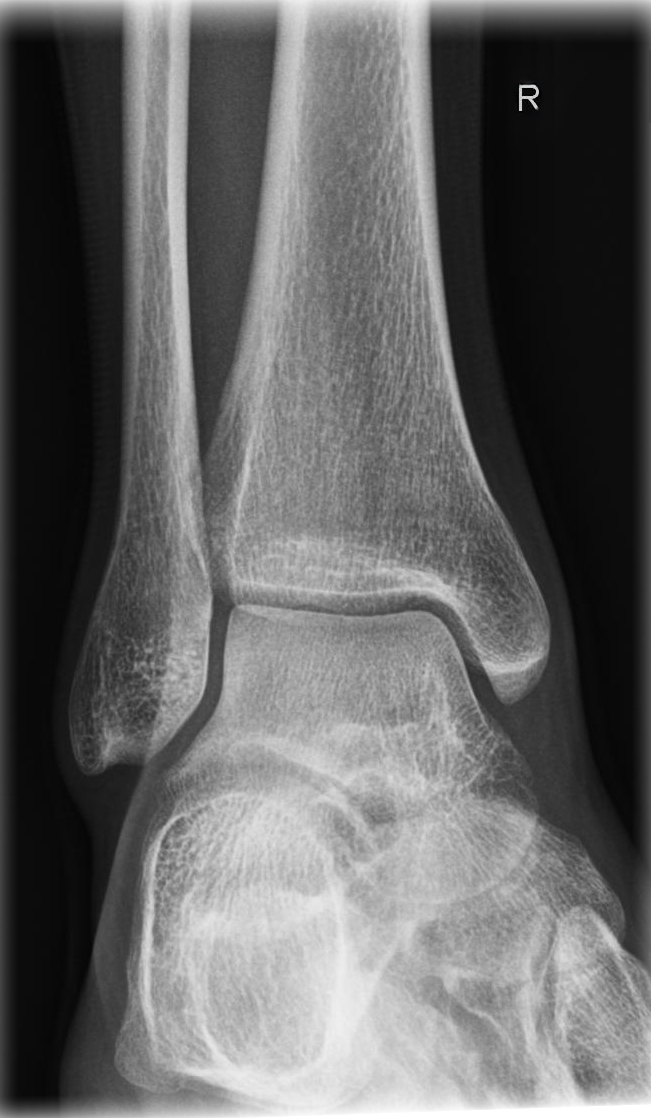

Oberes Sprunggelenk seitlich (2. Ebene)

Technik

• FDA: 1,05 m

• Ausgangsformat: 18/24

• Übertischaufnahme

Indikation

Fraktur, Bandverletzungen, Luxation

Lagerung

liegend auf Tisch

Bein liegt auf der aufzunehmenden Seite

Bein gestreckt, Fuß cranial anziehen (ca. 90° Winkel zum US)

Malleolus medialis und lateralis stehen senkrecht zueinander (C-Griff)

Zentralstrahl

senkrecht

Querzentrierung: Gelenkspalt

Längszentrierung: mittig über Malleolus medialis

Einblendung

proximal 5 QF, lateral 1 QF hinter Ferse

Qualitätskriterien

Oberes und unteres Sprunggelenk rein seitlich abgebildet mit Darstellung auch des Chopartgelenkes und des Calcaneus (Fersenbein). Planparallele Darstellung der Schienbeingelenkfläche und der Talusrolle (keine Doppelkonturen). Die Fibula projiziert sich in das mittlere bis hintere Drittel der Schienbeingelenkfläche.